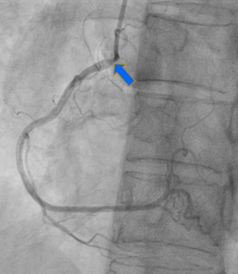

A 60 year-old infectious disease physician with history of Stage IIA Hodgkin Disease s/p radiation therapy in 1976 (age 13) presented to cardiology for new dyspnea on exertion. She had known valvular heart disease followed with serial echocardiograms. Repeat TTE completed showing now moderate to severe aortic stenosis, moderate aortic regurgitation, moderate tricuspid regurgitation, and mild to moderate mitral regurgitation. After exercise stress testing aborted due to decrease in systolic blood pressure with exertion, patient underwent cardiac catheterization and found to have moderate-severe aortic stenosis as well as hemodynamically significant ostial disease of the right coronary artery and distal left main coronary artery; classic bi-ostial coronary stenosis characteristic of RICAD. After multidisciplinary discussion with interventional cardiology, cardiothoracic surgery, and second opinion with tertiary valve center, she was referred for surgical revascularization and aortic valve replacement (AVR). Patient underwent AVR with a 23mm bioprosthetic aortic tissue valve replacement, aortic root enlargement, tricuspid valve repair with 28mm ring, and three vessel coronary artery bypass grafting.